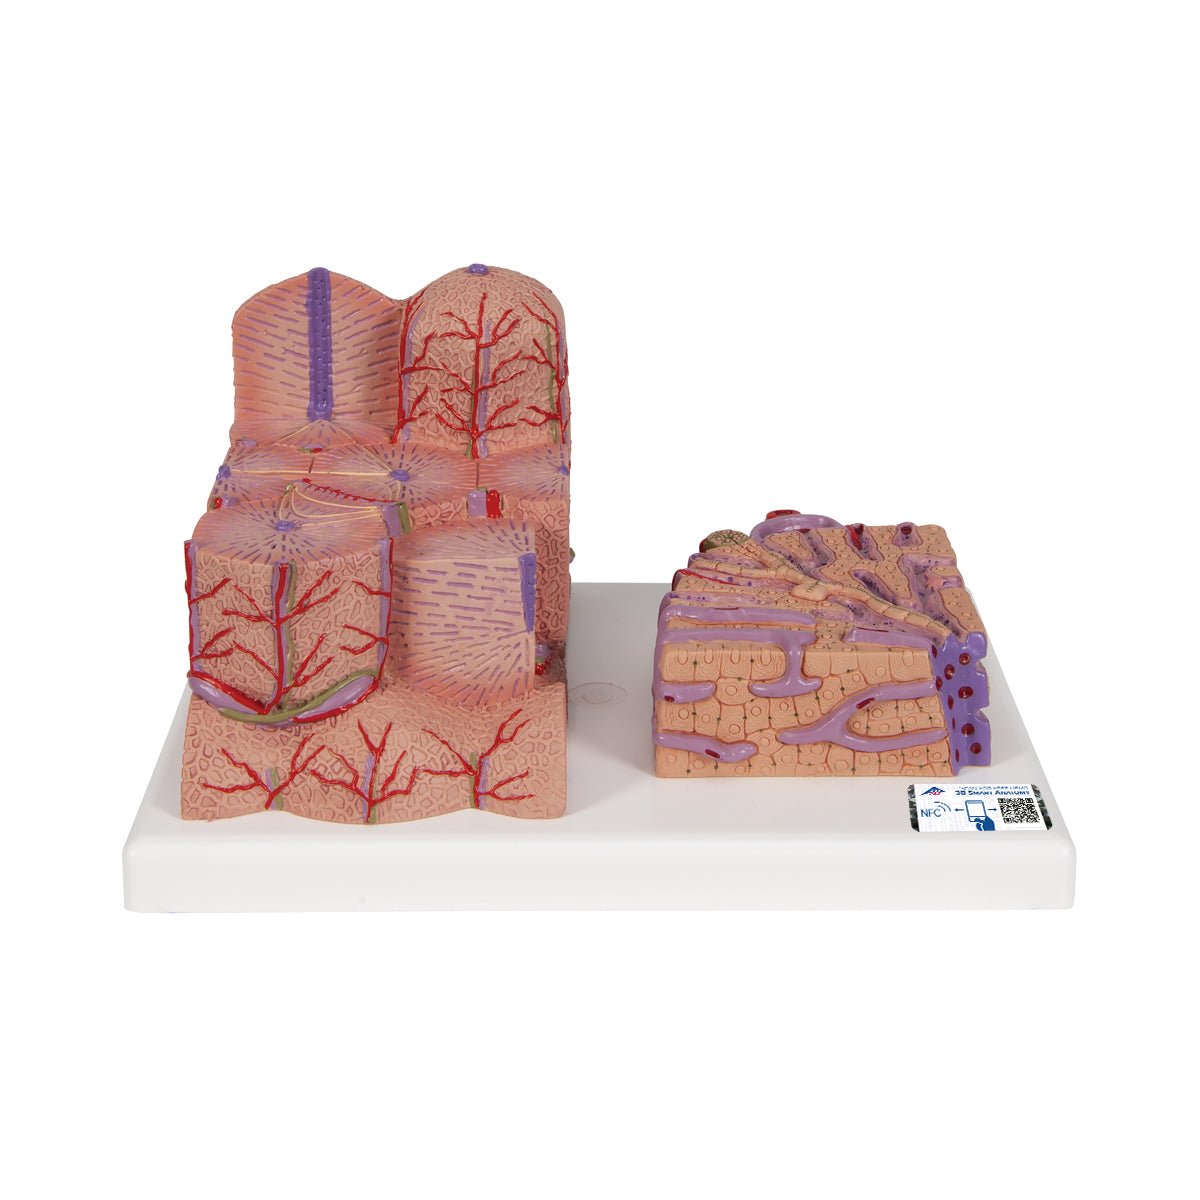

Salg af anatomiske modeller er det bærende element i eAnatomi, selvom vi også bruger mange ressourcer på at udvikle vores egne anatomiske materialer som fx plakater. Anatomiske modeller anvendes til forskellige formål og kan både vise afgrænset væv, organer samt organsystemer. Søger du en simpel model af knoglevæv eller måske en avanceret torso-model baseret på MRI teknologi, kan du finde det hele på eanatomi.com.